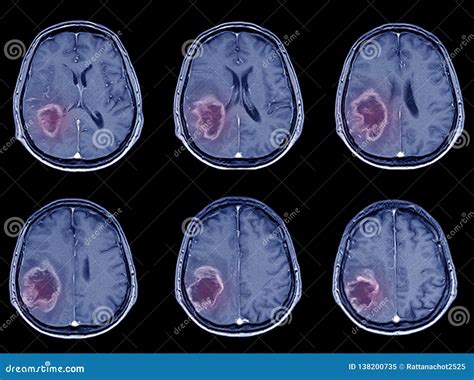

Later Signs of Ischemic Stroke on a CT Scan

As time passes, the changes on the CT scan become more apparent. The following signs are usually visible later:

• Hypodensity: Areas of the brain that are damaged due to the lack of blood flow will start to appear darker on the CT scan. This is called hypodensity. It indicates that the brain tissue is dying.

• Mass Effect: As the brain swells, it can push on other structures, causing a mass effect.

• Infarct: This is a term for the area of dead tissue caused by the stroke. It can be seen as a clearly defined dark area on the scan.

Differentiating Ischemic vs. Hemorrhagic Stroke

One of the main goals of the CT scan is to differentiate between an ischemic stroke and a hemorrhagic stroke. A hemorrhagic stroke involves bleeding in the brain. On a CT scan, blood appears bright white. So, if the scan shows any bright white areas, it’s a sign of bleeding. If there’s no bleeding and the scan looks relatively normal (or shows the signs of ischemic stroke ), then it’s most likely an ischemic stroke . This distinction is super important because the treatments for each type of stroke are different.